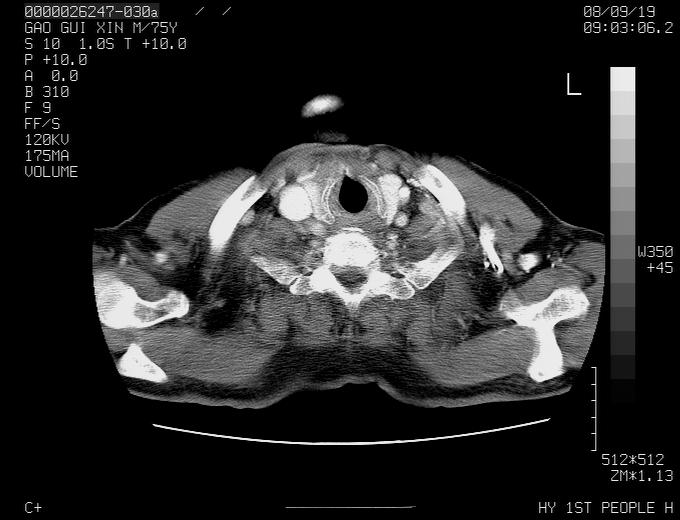

感谢各位老师的意见,左上肺病灶,我本人趋向结核,原因:左上肺见两个类圆形结节,仔细回顾4月份ct似乎原片在该处有条片状密度增高影,强化不明显。

现上传增强片,请各位老师仔细帮我看一下。

右上肺可见条索状影,并可见钙化,左上肺结节可以考虑为结核球,但气管前腔静脉后有肿大淋巴结,本人觉得左上肺结节不能排除转移瘤的可能,右上肺为陈旧性结核灶。

左肺上叶周围性肺癌并纵隔多组lnm.不可能是tb.

左肺上叶尖段瘢痕癌并纵隔淋巴结转移解释更好一些.

双上肺继发型肺结核,纵隔淋巴结结核可能性大,建议定期复查.

左肺周围癌并纵隔淋巴结转移,另一小结节是血管影

别再ct讨论了,一个纤支镜检查马上明确.肺癌不会错的!应该是低分化鳞癌.

左上肺周围型肺癌并纵隔淋巴结转移

1)左肺上叶尖段周围型肺癌并纵隔淋巴结转移。2)冠状动脉及主动脉钙化。

左上肺周围型肺癌并纵隔淋巴结转移。纤支镜检查